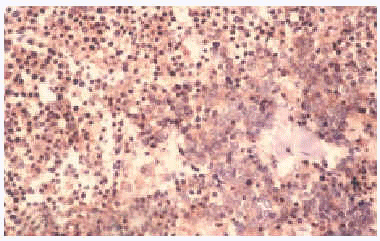

Histológicamente mostraron una disposición dérmica en sábanas o racimos que afectaba a epidermis, en algunos casos. Se registraron 2 casos de invasión linfática. En la mayoría de los casos el tumor estaba formado por pequeñas células basófilas con núcleo redondo y vesicular con cromatina dispersa y nucléolos pequeños periféricos junto con escaso citoplasma (figs. 2 y 3). Las figuras mitóticas fueron en todos los casos muy notables, acompañadas por fenómenos de apoptosis. El estroma presentaba proliferación vascular en forma de fino entramado capilar con endotelios reactivos. En uno de los casos (paciente 2), la histología presentó características peculiares con un patrón epitelioide fusocelular y disposición en trabéculas.

Fig. 2.--Patrón histológico del carcinoma de células de Merkel.

Fig. 3.--Patrón histológico del carcinoma de células de Merkel (HE, x200).